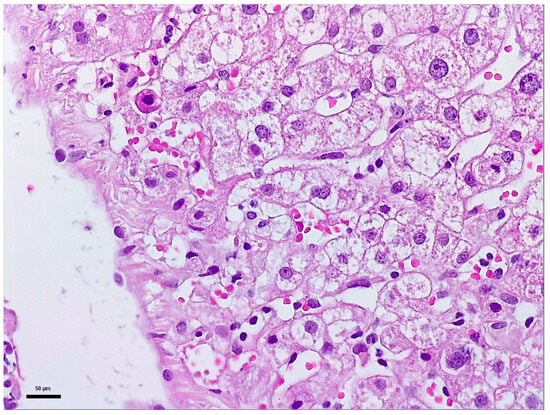

Diffusion Basis Restricted Fraction as a Putative Magnetic Resonance Imaging Marker of Neuroinflammation: Histological Evidence, Diagnostic Accuracy, and Translational Potential -